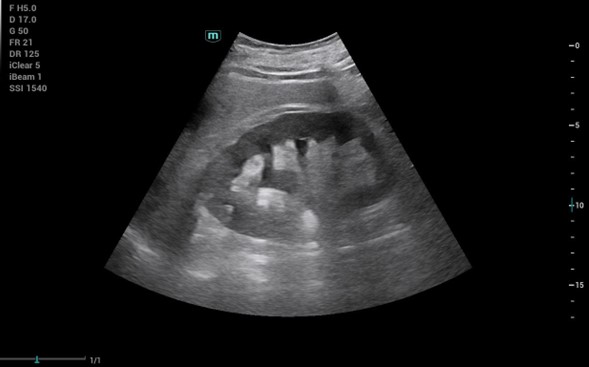

1. Hombre de 84 años con disnea progresiva de 6 meses de evolución: neoplasia pulmonar estadio IV con metástasis óseas.